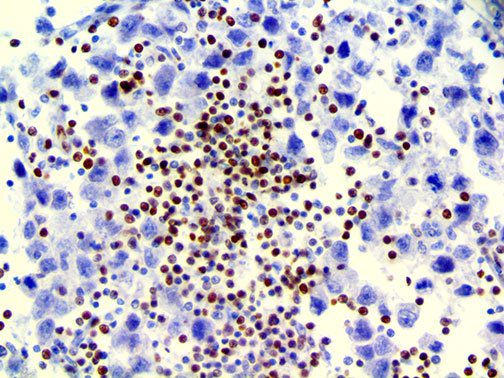

It is the ICU physician who is most likely to witness one of the deadliest manifestations of the abnormal immunological response, the cytokine storm syndrome (CSS). This response is also referred to by some as the cytokine release syndrome (CRS). CSS is characterized by continuous activation and expansion of macrophage and lymphocyte populations, which secrete large amounts of cytokines, causing the cytokine storm. This massive cytokine release is akin to hemophagocytic lymphohistiocytosis (HLH) disease, a syndrome characterized by initial unchecked and persistent activation of cytotoxic T lymphocytes and NK cells.

Clinical and laboratory manifestations of HLH include fever, enlarged liver and/or spleen, neurologic dysfunction, coagulopathy, liver dysfunction, cytopenias (i.e., low levels of erythrocytes, leukocytes, and/or platelets), hypertriglyceridemia, hyperferritinemia, hemophagocytosis, and eventually diminished NK cell activity as the immune system becomes progressively paralyzed. HLH can be familial (primary HLH) or secondary to another disease process (sHLH), such as rheumatic disease, in which it is referred to as macrophage activation syndrome (MAS, characterized by elevated ferritin).